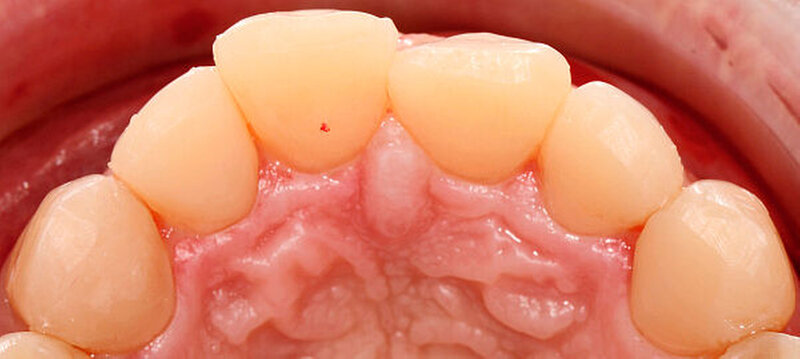

Nach Kofferdamapplikation wurde die Bisshebung im Seitenzahnbereich mit direkten okklusalen Kompositaufbauten (Tabletops) mit dem Kompositmaterial Filtek Supreme XTE (3M Espe) und dem Adhäsivsystem Optibond FL (Kerr) durchgeführt. Der Aufbau erfolgte dabei Zahn für Zahn unter Zuhilfenahme der Übertragungsschienen. Um ein interdentales Verblocken zu verhindern, wurden jeweils die Nachbarzähne der zu restaurierenden Zähne mit Teflonband isoliert (Abbildung 3).

Die Kompositoberflächen der Zähne wurden entsprechend des Vorgehens bei einer Korrekturfüllung mit einem Sandstrahler (SiO2-Pulver) angeraut und silanisiert. Die erodierten beziehungsweise sklerotisch veränderten Dentinoberflächen wurden vor der Applikation des Adhäsivsystems mit einem Feinkorndiamanten zur Verbesserung der Haftkräfte angefrischt [Camargo et al., 2008; Zimmerli et al., 2012]. Das Komposit wurde in einer der fehlenden Zahnsubstanz entsprechenden Menge in die Schiene eingebracht und unter einem Lichtschutz für etwa fünf Minuten auf einer Wärmeplatte (Calset; AdDent) erwärmt. Durch das Erwärmen wird die Viskosität des Komposits reduziert und damit die Positionierung der Schiene erleichtert, ohne dass die Materialeigenschaften des Komposits beeinträchtigt werden [Tauböck et al., 2015].

Die Lichtpolymerisation erfolgte durch die Schiene hindurch für zunächst nur etwa drei bis fünf Sekunden. Nach Abnahme der Schiene wurden Überschüsse des noch nicht vollständig polymerisierten Kompositmaterials mit einem Skalpell entfernt. Anschließend wurde eine gründliche (zweite) Polymerisation für 60 Sekunden durchgeführt. Neue Untersuchungen konnten zeigen, dass durch diese zweizeitige – sogenannte Pulse-Delay-Polymerisation – die Qualität des Komposits nicht reduziert wird [Tauböck et al., 2014].

Die schwer zugänglichen Approximalflächen und -übergänge wurden mit oszillierenden, einseitig diamantierten Feilen ausgearbeitet und geglättet. Mit dieser Technik wurden die Seitenzähne im Ober- und im Unterkiefer schrittweise aufgebaut und abschließend poliert (Abbildung 4).